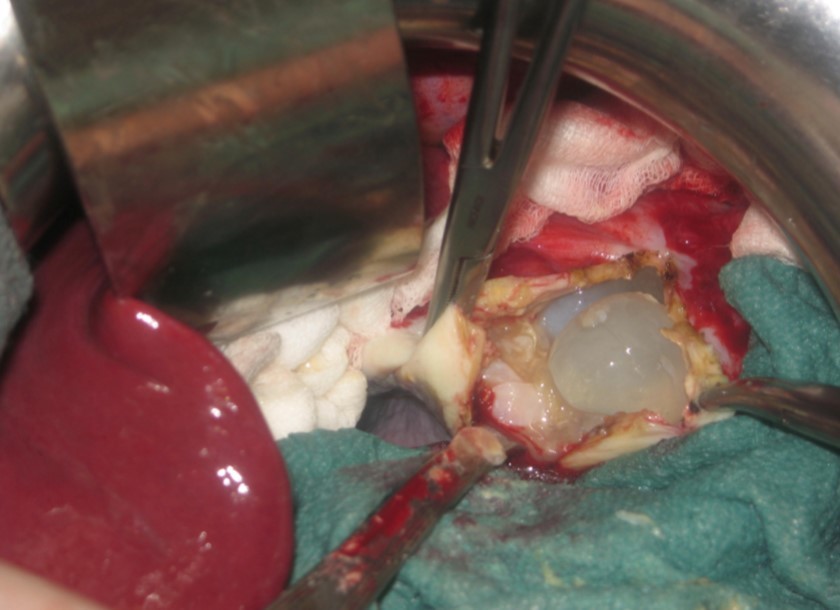

A 17-year-old young man admitted to our department with the complaint of abdominal pain localized in the left upper quadrant for the last 3 months. His physical examination revealed a splenomegaly. Immunoblot assay for Echinococcus was positive. His laboratory tests showed normal results of the serum and urine examinations, No eosinophilia was found. Chest X-ray revealed no pathological signs. An abdominal ultrasonography showed a 20 cm multivesicular cystic mass of spleen (figure 1). Contrast enhanced CT scans detected a huge single 20×16×18cm cystic mass located in the spleen. It had well-defined borders and contained multiple, round, daughter cysts in the periphery of the lesion with calcification (Figure 2, Figure 3, Figure 4). The patient underwent a laparotomy. A large splenic cystic mass was identified, attached to diaphragm, and tail of the pancreas (figure 5). The abdomen was packed with 10% hypertonic saline soaked pads in order to protect peritoneal soilage. A partial cystectomy without splenectomy was performed. Histologic examination of the specimen resection showed an echinococcal organism residing within the hydatid cyst . The patient was discharged after 4 postoperative days. 600 mg per a day of Albendazole therapy was instaured postoperatively and continued for 6 months. Two years after surgery the patient is well with disease free.

Figure 5.Intraoperative view showing multivesicular spleen hydatid cyst.